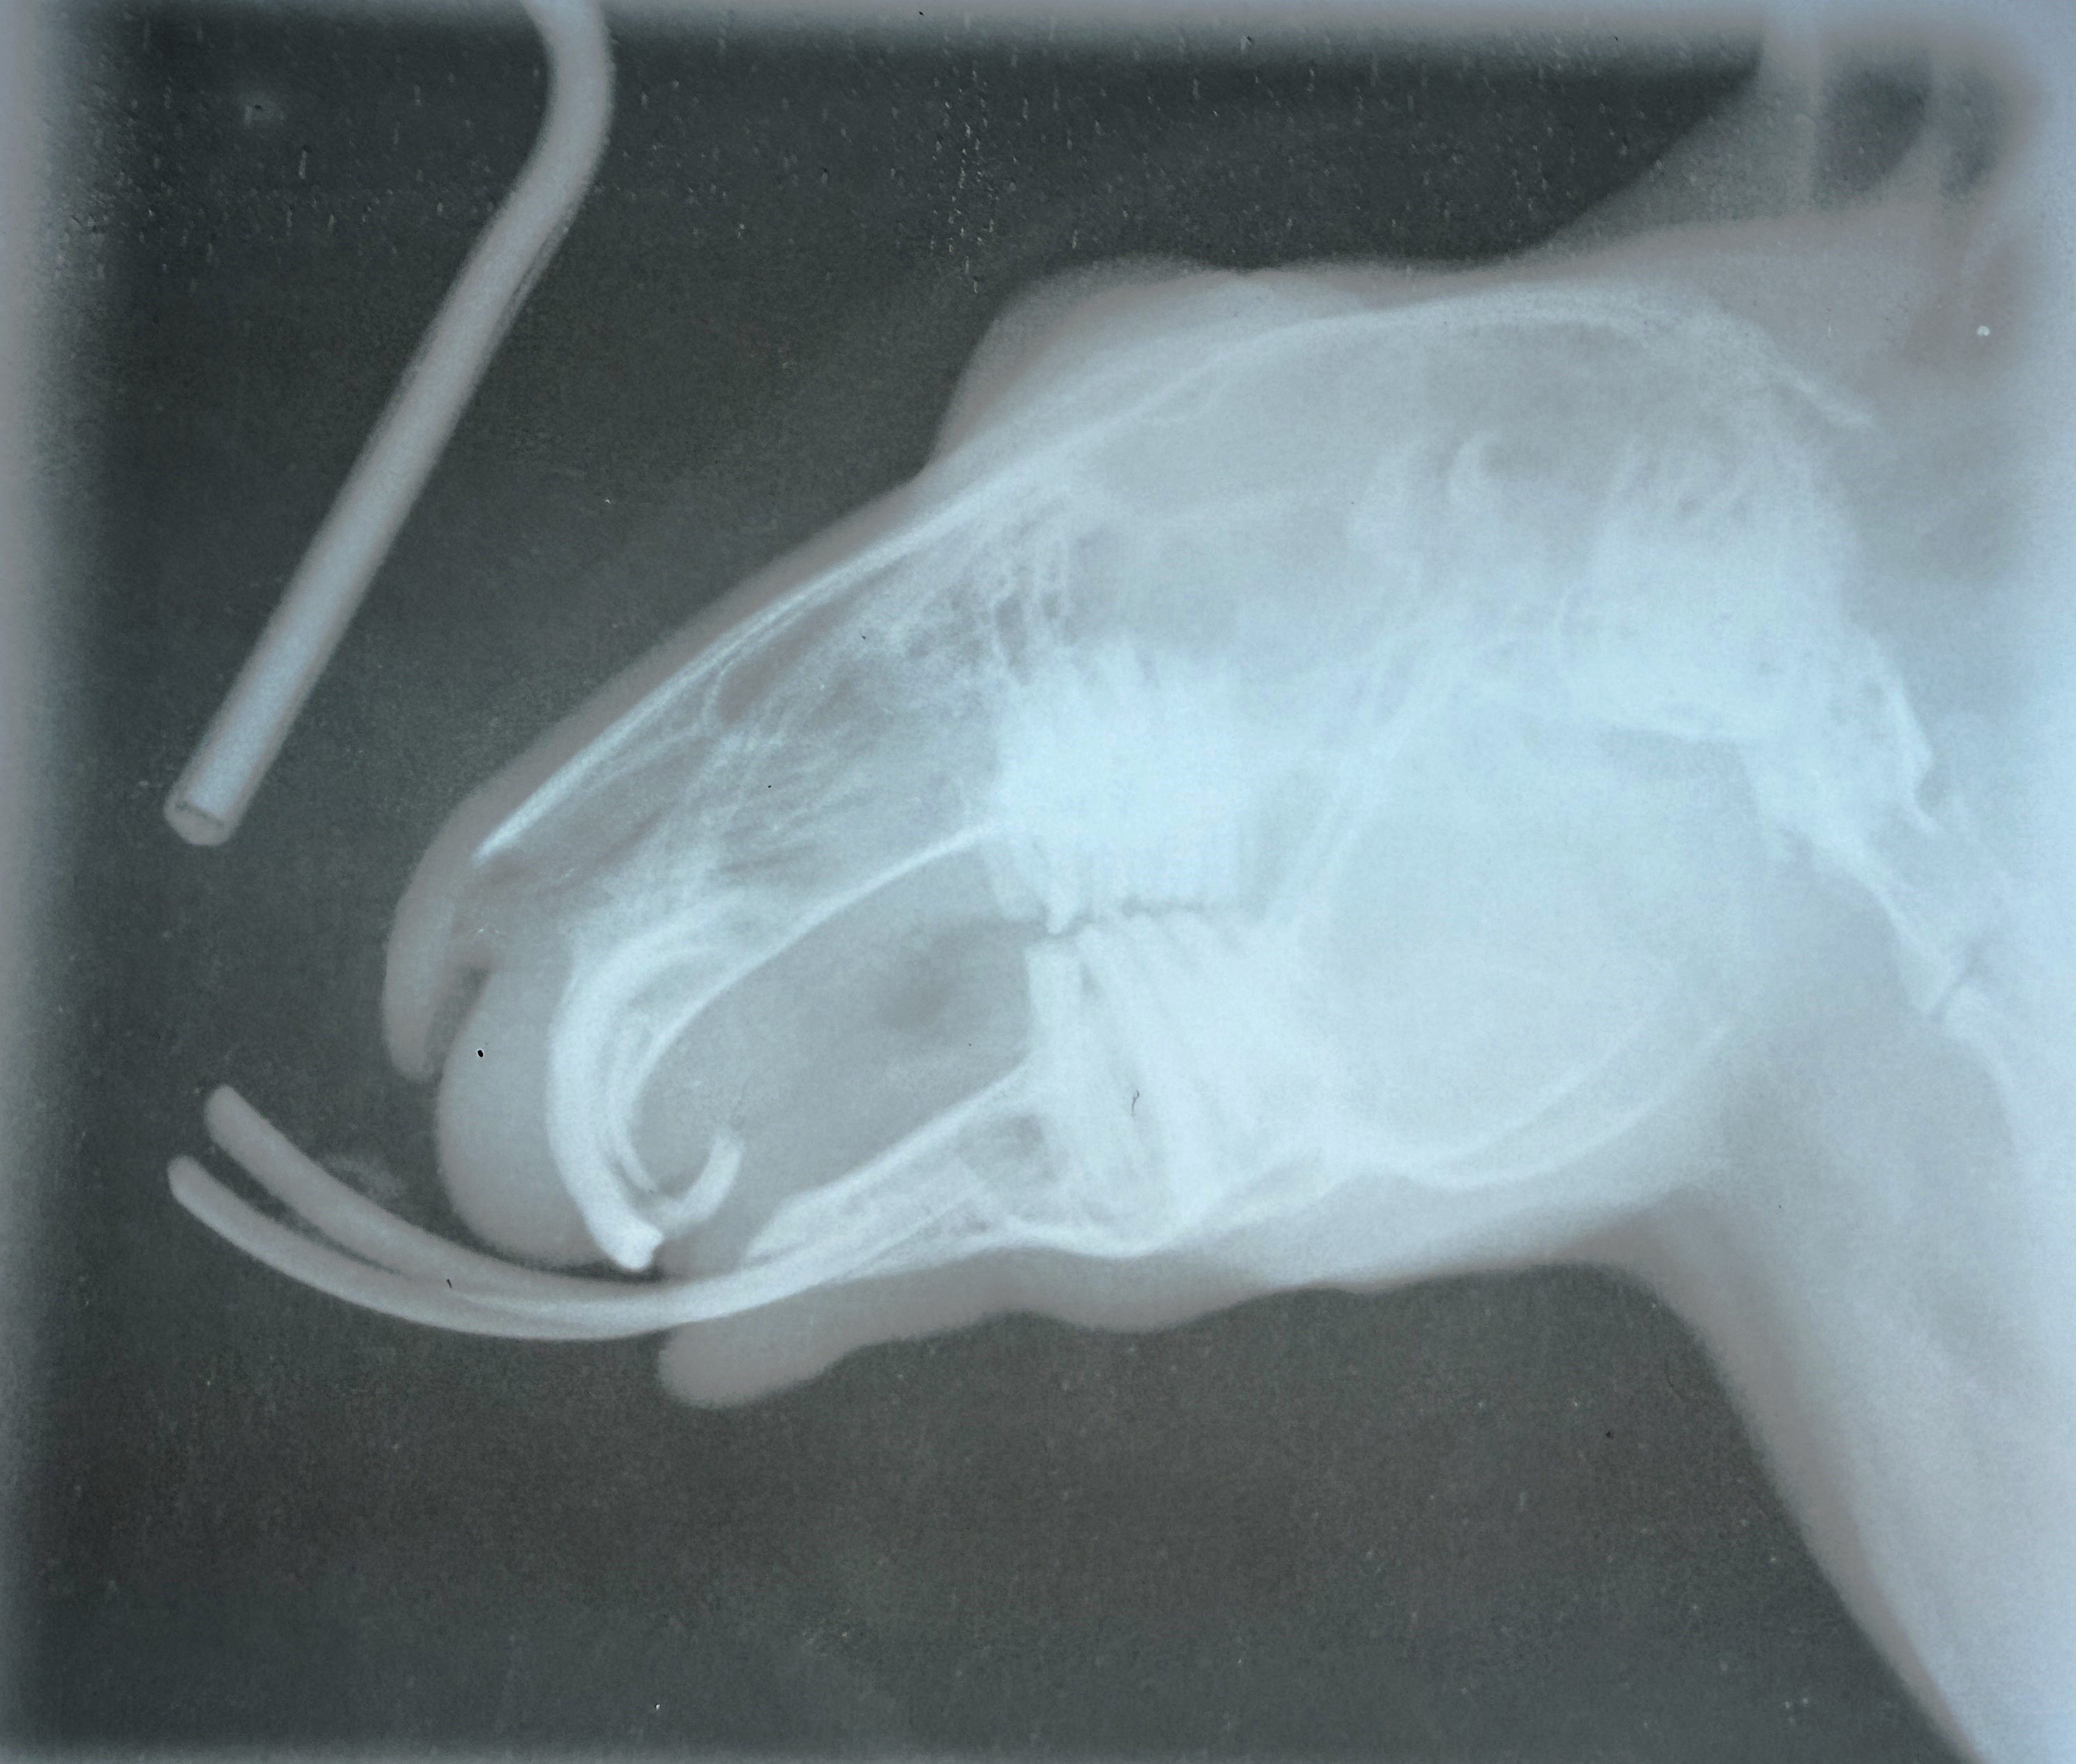

1. Once your patient is anesthetized, take skull radiographs to evaluate the apices of the teeth. In young rabbits, extraction is typically straightforward, however in older rabbits, the teeth can be abscessed or ankylosed to the surrounding bone. Radiographs help determine if extraction is possible. This is also a good opportunity to further evaluate the cheek teeth.

This is a film radiograph (what we can get in Belize!) and the technique isn't quite right - but it gives you an idea of how we can use radiographs to evaluate the curvature of the teeth, and check for the presence of sclerosis or apical lucency. It's a bit difficult to tell in this image, but there is a lucency at the base of the mandibular incisors, consistent with the abscess I found clinically on removal of the left mandibular incisor.